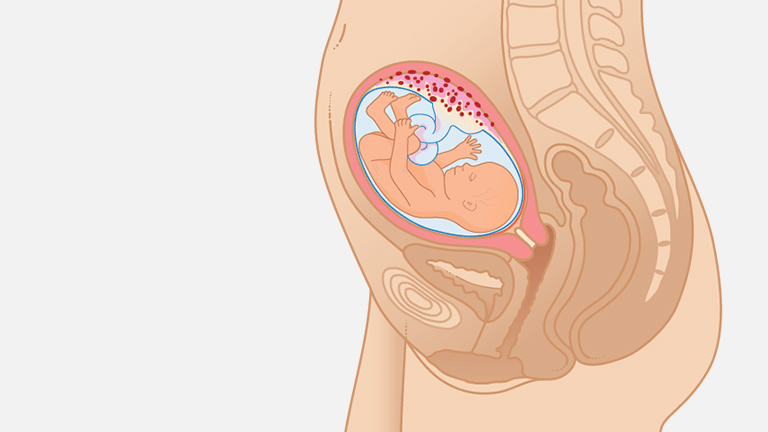

وضعیت جنین در هفته نوزدهم بارداری

نکته جالبی که در مورد وضعیت جنین در این هفته وجود دارد این است که بااینکه هیچ ماده غذایی داخل کیسه آب وجود ندارد اما بازهم جنین شما حس چشایی دارد و بقیه حسها مثل بویایی و لامسه از این هفته در او فعال میشوند؛ ولی او هنوز نمیتواند از این حسها استفاده کند.

بنابراین در هفته نوزدهم بارداری سلولهای عصبی روی حسهای پنجگانه جنین فعالیت دارند و چون اعضای بدن به تعادل موردنظر رسیدهاند، دیگر پاهای کوچک و کله بزرگ در بدن جنین نمیبینید.

حالا همه اجزا بهاندازهای که باید رشد کردهاند و پوست جنین هم با استفاده از مادهای به نام ورنیکس پوشیده شده که حالت سفید و لغزنده دارد و کمک میکند بدن جنین شما از خشکی محافظت شود. این پوشش لیزر و نرم باعث میشود کودک شما در هنگام زایمان در مجرای زایمان راحتتر حرکت کند.

همچنین در این زمان سیمپیچیهای مغز جنین هم شکل گرفته و ارتباط بین رشتههای عصبی عضلات و مغز برقرار شده است و دیگر این توانایی را دارد که اعضای بدن خود را کنترل کند.

مایع مغزی نخاعی که در اطراف نخاع و مغز قرار گرفته در شبکه عروقی مغز تشکیل شده است و جوانههای دندانهای دائمی نیز پشت دندانهای شیری رشد کردند و جنین خیلی راحت مایع آمنیوتیک را مینوشد.

از هفته نوزدهم بارداری رودههای جنینتان هم کار خود را آغاز میکنند و با ترشح کردن شیره روده جذب مایع آمنیوتیک بالاتر میرود و کلیهها این مایع را تصفیه میکنند و کودک دیگر میتواند درون آب آمنیون ادرار کند و نیازی به نگرانی از این بابت نیست چون هر چند ساعت یکبار این مایع تصفیه میشود.

درصورتیکه فرزند شما دختر باشد 6 میلیون تخمک درون دستگاه تناسلی انباشته شده که موقع تولد به 2 میلیون تخمک خواهد رسید. با توجه به رشدی که بدن جنین دارد از هفته نوزدهم به بعد کمتر میتوانید رگهای بدن او را ببینید و رنگدانههای پوستی به اسم ملانوسیت هم کار خود را در هفته نوزدهم آغاز کردند و حالا دیگر قد جنین شما 15.7 سانتیمتر و وزن او 243 گرم است.

بیشترین اضافهوزنی که در بدن مادر در هفته نوزدهم رخ میدهد اطراف شکم و باسن است که حدود 3 تا 6 کیلوگرم است و وزن جفت در این زمان حدود 170 گرم هست و مایع آمنیوتیک و رحم حدود 350 گرم بهصورت مجزا وزن دارند.

با توجه به اینکه وزن سینههای شما هم در هفته نوزدهم بیشتر شده، به 180 گرم رسیده است و گاهی اوقات احساس میکنید شکمتان آنقدر بزرگ شده که پوستتان کش میآید اما باید بدانید هنوز افزایش سایز بیشتری خواهید داشت و تا هفته چهلم هرروز کمی شکم شما بزرگتر خواهد شد تا جای کافی برای رشد جنین وجود داشته باشد.